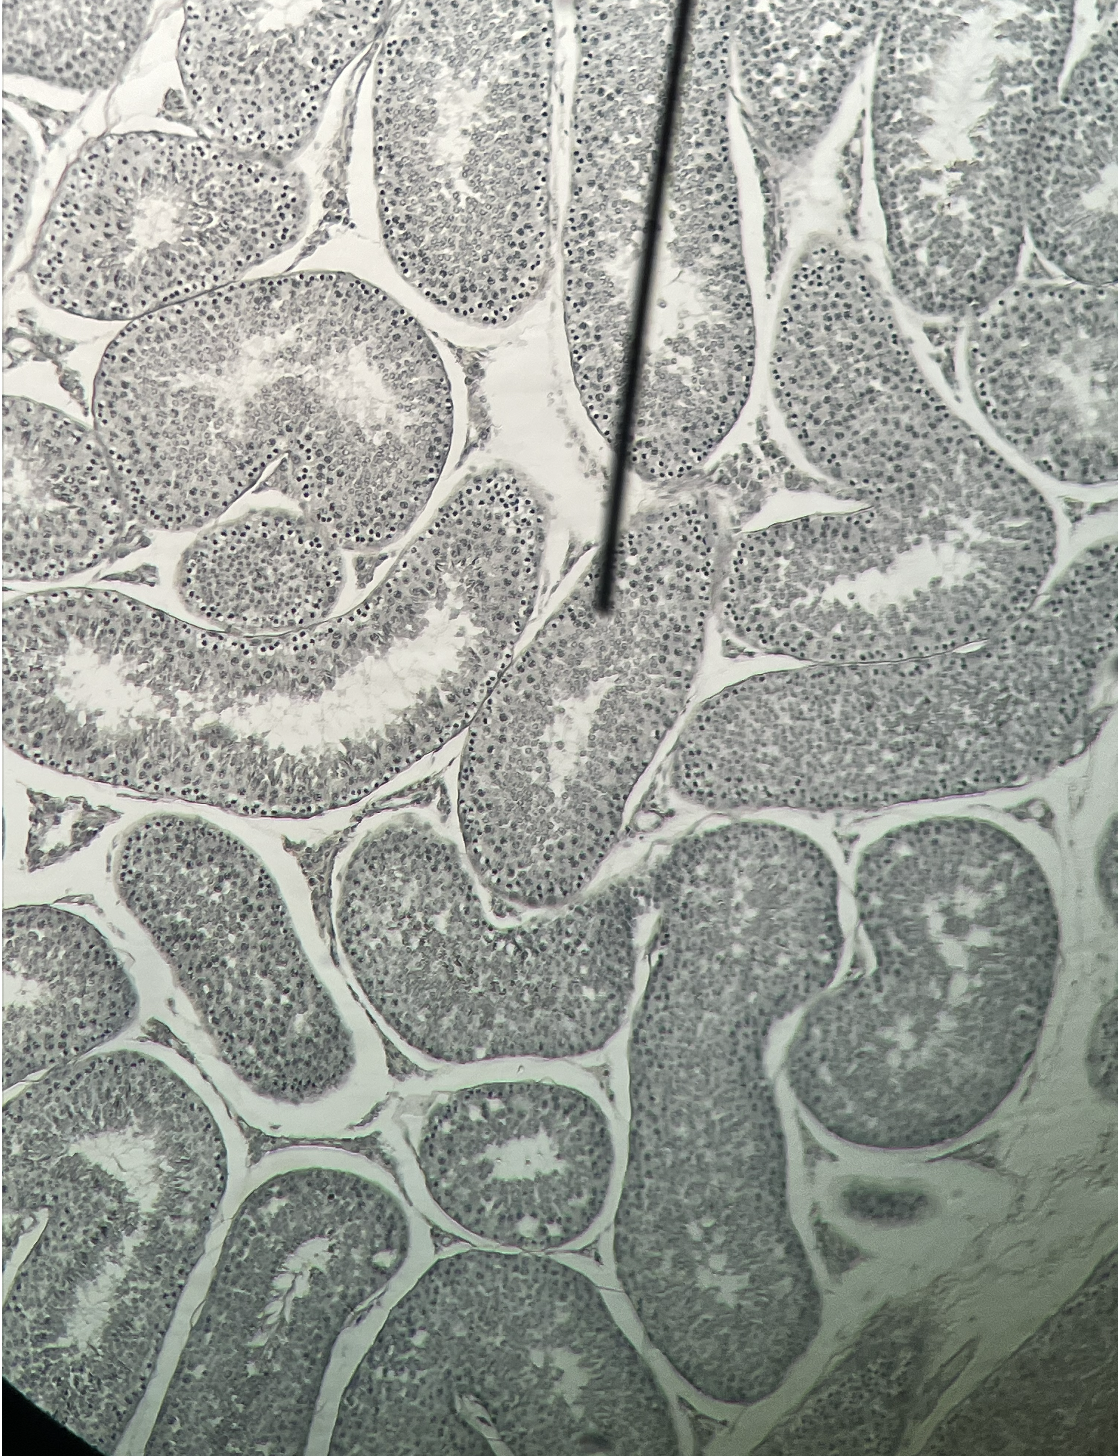

testes

knowt flashcard image